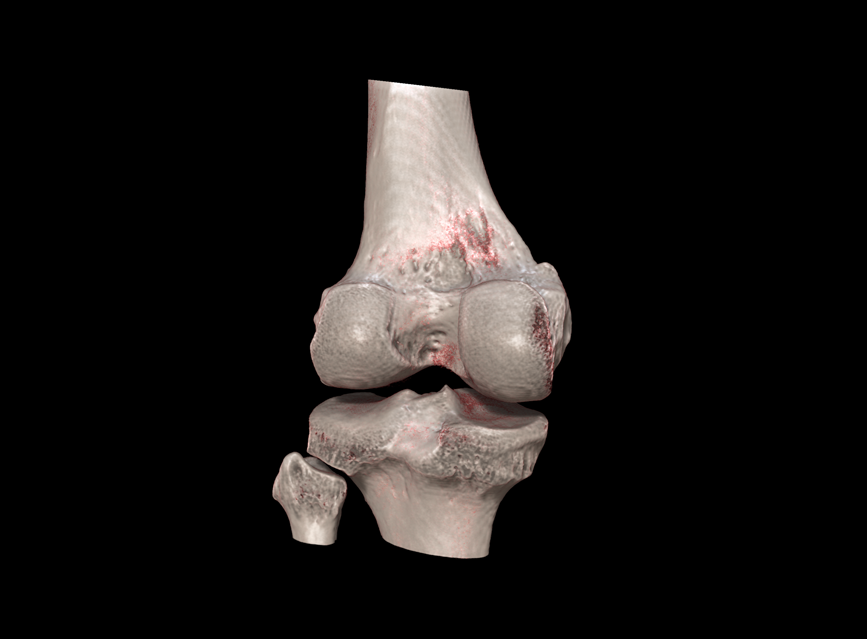

HRCT

High Resolution Computed Tomography. Outstanding image quality with a voxel size up to 100 µm